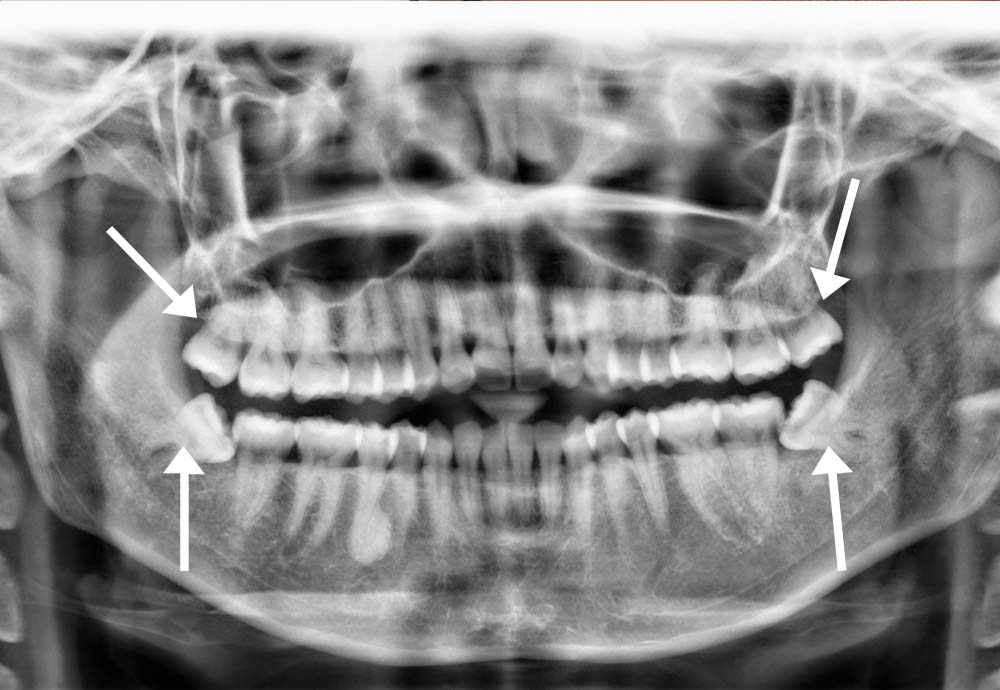

Some lower wisdom teeth can be close to the inferior alveolar nerve (which gives feeling to your lip & chin).

In rare cases, this may cause temporary symptoms such as:

Wisdom tooth removal is generally safe, but like any surgical procedure, there are some risks such as nerve irritation and infection.

In rare cases, lower wisdom teeth may be close to a nerve, which could cause temporary numbness. To improve safety, we use Piezo-assisted surgery and laser disinfection, which help protect nearby tissues and support faster healing.